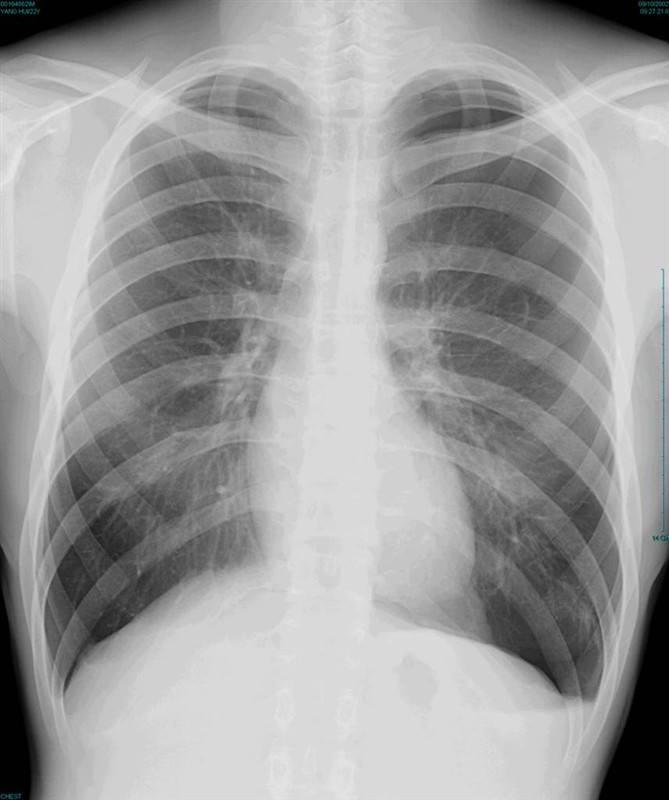

照片名称:正常胸片

照片名称:正常x光胸片